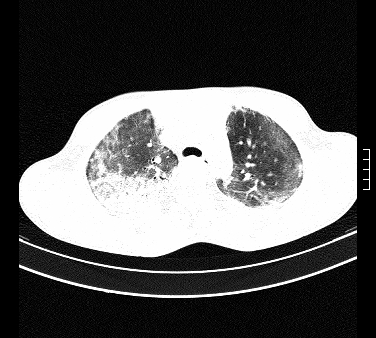

标题: CT15133:M17Y,百草枯中毒患者,典型病例分享 [打印本页]

标题: CT15133:M17Y,百草枯中毒患者,典型病例分享

患者,男,17岁,系我院急诊科收治的一例百草枯中毒患者,做ct检查时,距离服药的时间为3天。上传与大家分享

补充:百草枯进入人体内主要分部于肺和骨骼,肺部损伤24小时内出现水肿,2-3天内出现急性呼吸窘迫综合征,1-2周内出现肺纤维化。(引自陈灏珠,实用内科学12版)

不错,挺好。符合呼吸窘迫综合征